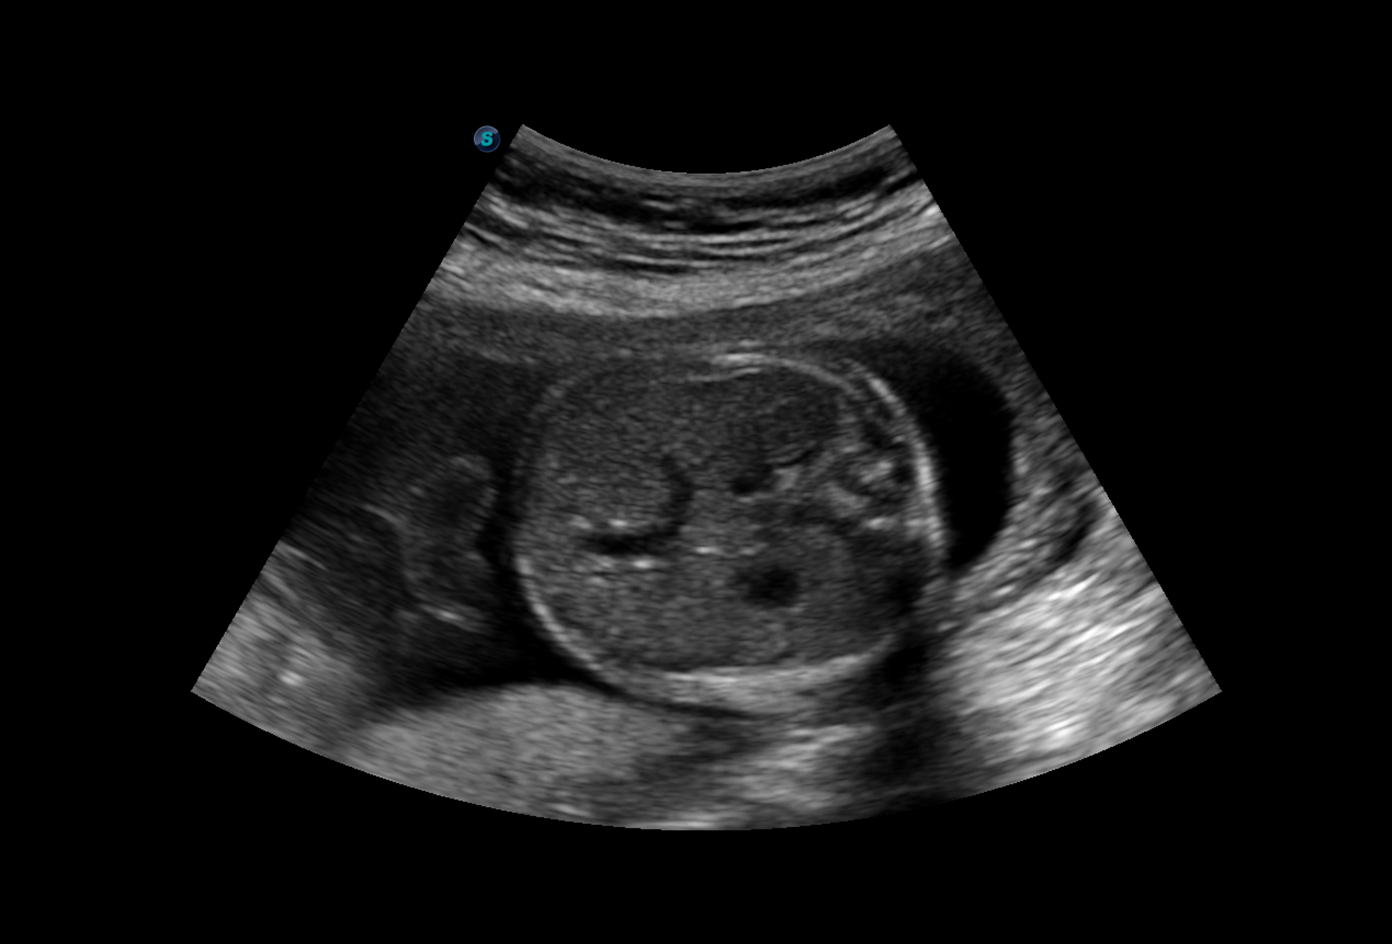

Không chỉ giới hạn trong tim mạch, SonoScape P9 còn được ứng dụng trong nhiều chuyên ngành khác như sản khoa, ngoại khoa và nhi khoa. Trong sản khoa, máy giúp theo dõi nhịp tim thai, đánh giá sự phát triển của thai nhi và tình trạng sức khỏe thai phụ. Trong ngoại khoa, thiết bị hỗ trợ bác sĩ định vị chính xác vị trí tổn thương, giúp phẫu thuật được thực hiện an toàn hơn.

Chất lượng hình ảnh 2D trên máy siêu âm chuyên tim SonoScape P9: